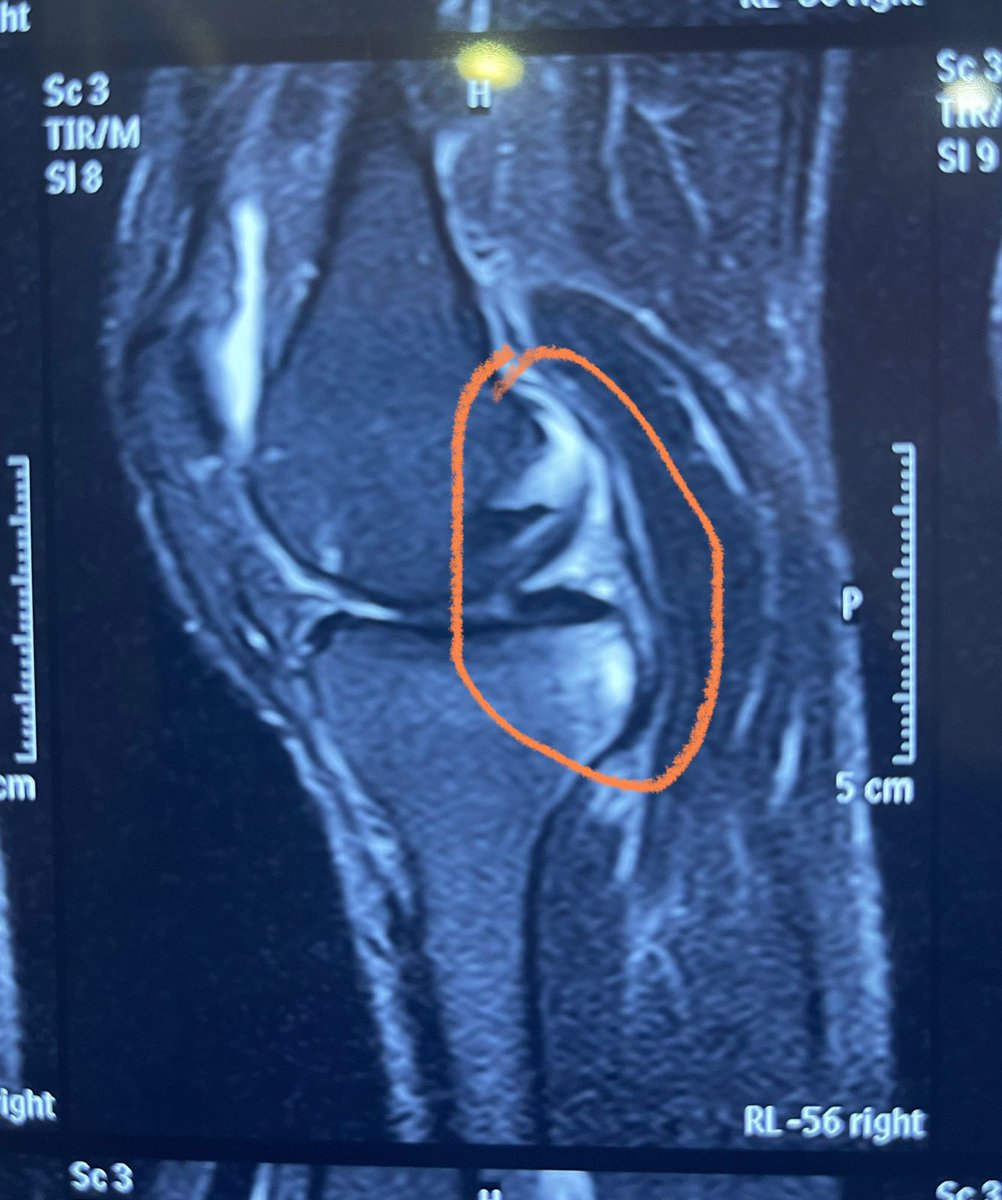

Konda Vishweshwar Reddy

Konda Vishweshwar Reddy@KVishReddy·

Had a knee meniscus tear 6 months ago. Neglected it, the tear got bigger. Had a Minimal invasive knee surgery last night. In the hospital till Monday. Could not postpone it further. Will be back in action in two weeks.

Konda Vishweshwar Reddy tweet mediaKonda Vishweshwar Reddy tweet mediaKonda Vishweshwar Reddy tweet media